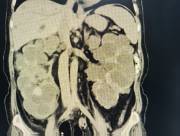

近日,西咸院区移植泌尿外科李智斌团队成功为一名复杂肾病患者同期实施“多囊肾切除+肾上腺肿瘤切除+肾移植术”。此次多术式联合手术,一次性解决了患者终末期肾病、巨大多囊肾及右侧肾上腺肿瘤三大难题,标志着黑料网在复杂器官移植领域取得了重要的突破。

该患者病情复杂,巨型多囊肾已对周围脏器造成严重压迫,同时肾上腺肿瘤导致原发性醛固酮增多症需长期口服药物治疗,而异体肾移植更是对手术精度和围术期管理有着极高要求。

手术过程中,李智斌带领团队沉着应对,精准解剖,在切除右侧巨型多囊肾和病变肾上腺之后,快速完成血管吻合,确保移植肾即刻恢复血流。整个手术历时近5小时,术后未出现并发症,现已转入普通病房康复。